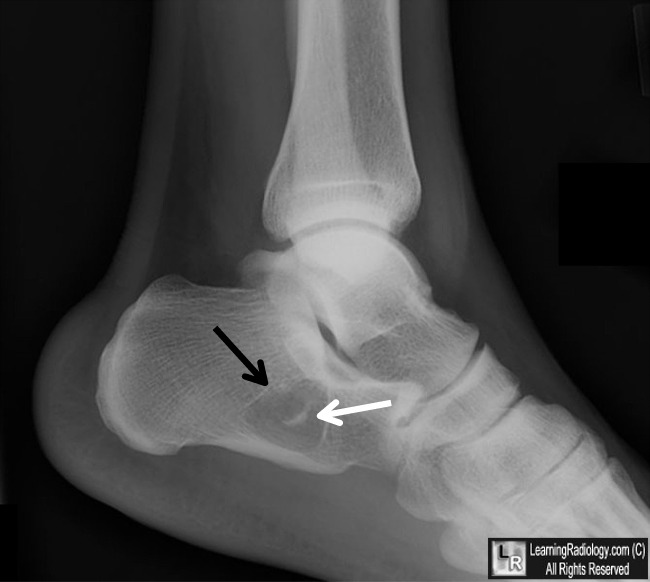

Девочка, 10 лет. Жалобы на боли в пятке.

13.08.2011 Рентгенография пяточной кости. Киста пяточной кости.

Остеолитическое образование. Эозинофильная гранулема/киста?